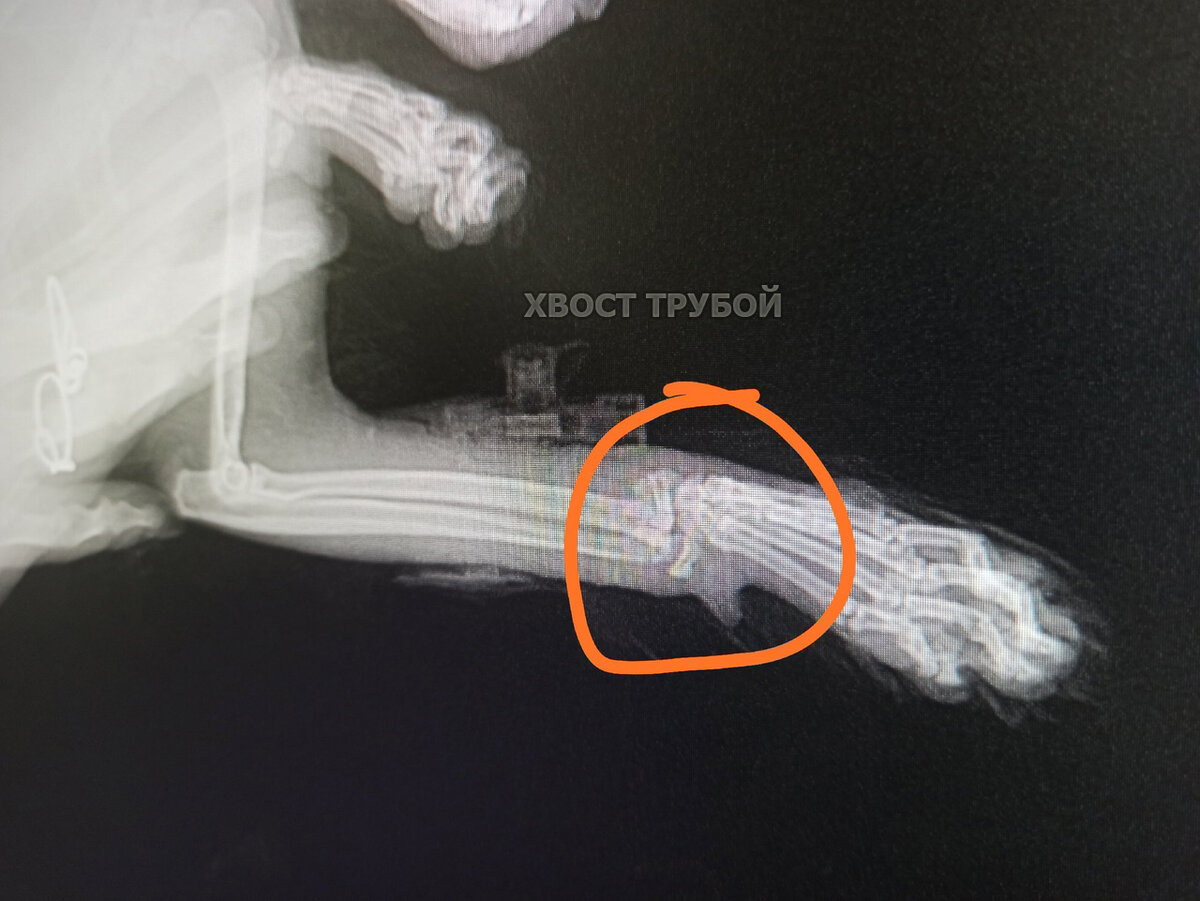

Она улетела в окно, когда хозяева что-то бурно праздновали. В ветклинику малышку привезли друзья хозяев, оказалось, что у бедняжки сло маны аж 3 лапки! Две передние и одна задняя. Кошечка приземлилась на лапы, это спасло ей жизнь, но лапки сильно пострадали. Оставив несчастную бедолагу в стационаре ветклиники, друзья хозяев уехали. А дальше началось нечто странное: сначала котейкой интересовались, потом неохотно брали трубку, потом и вовсе перестали отвечать на звонки.

Она улетела в окно, когда хозяева что-то бурно праздновали. В ветклинику малышку привезли друзья хозяев, оказалось, что у бедняжки сло маны аж 3 лапки! Две передние и одна задняя. Кошечка приземлилась на лапы, это спасло ей жизнь, но лапки сильно пострадали.

Наверное стоит пояснить, а то в комментариях уже открылись врата ада. Ляля не просто лежала в стационаре, как некоторым читателям показалось. За ней оказывался должный уход, ей делались капельницы, ей подмывали попу, потому что она не могла нормально сходить в туалет и не испачкаться, ей меняли пелёночки, ее даже первое время кормили из шприца, потому что она сама не ела. Сами операции в данном случае ее боль не облегчили бы. Как видно на первых фото, кошка находится в шоковом состоянии, в первые дни ее в любом случае бы не оперировали, а стабилизировали состояние. Чем, собственно, врачи и занимались. Две передние лапки начали срастаться самостоятельно. На задней лапке операция проведена сразу же, как только был получен письменный отказ хозяев от кошки. Мы не можем расписывать красочно все проводимые манипуляции и диагнозы, на Дзене есть определенные правила работы с каналами.

От Ляли, наконец-то, написали отказную, оплатили счета за стационар, и с момента отказа малышка находится под нашей опекой и кураторством. Ей провели операцию на одной задней лапке, передние уже нет смысла оперировать, косточки начали срастаться сами.